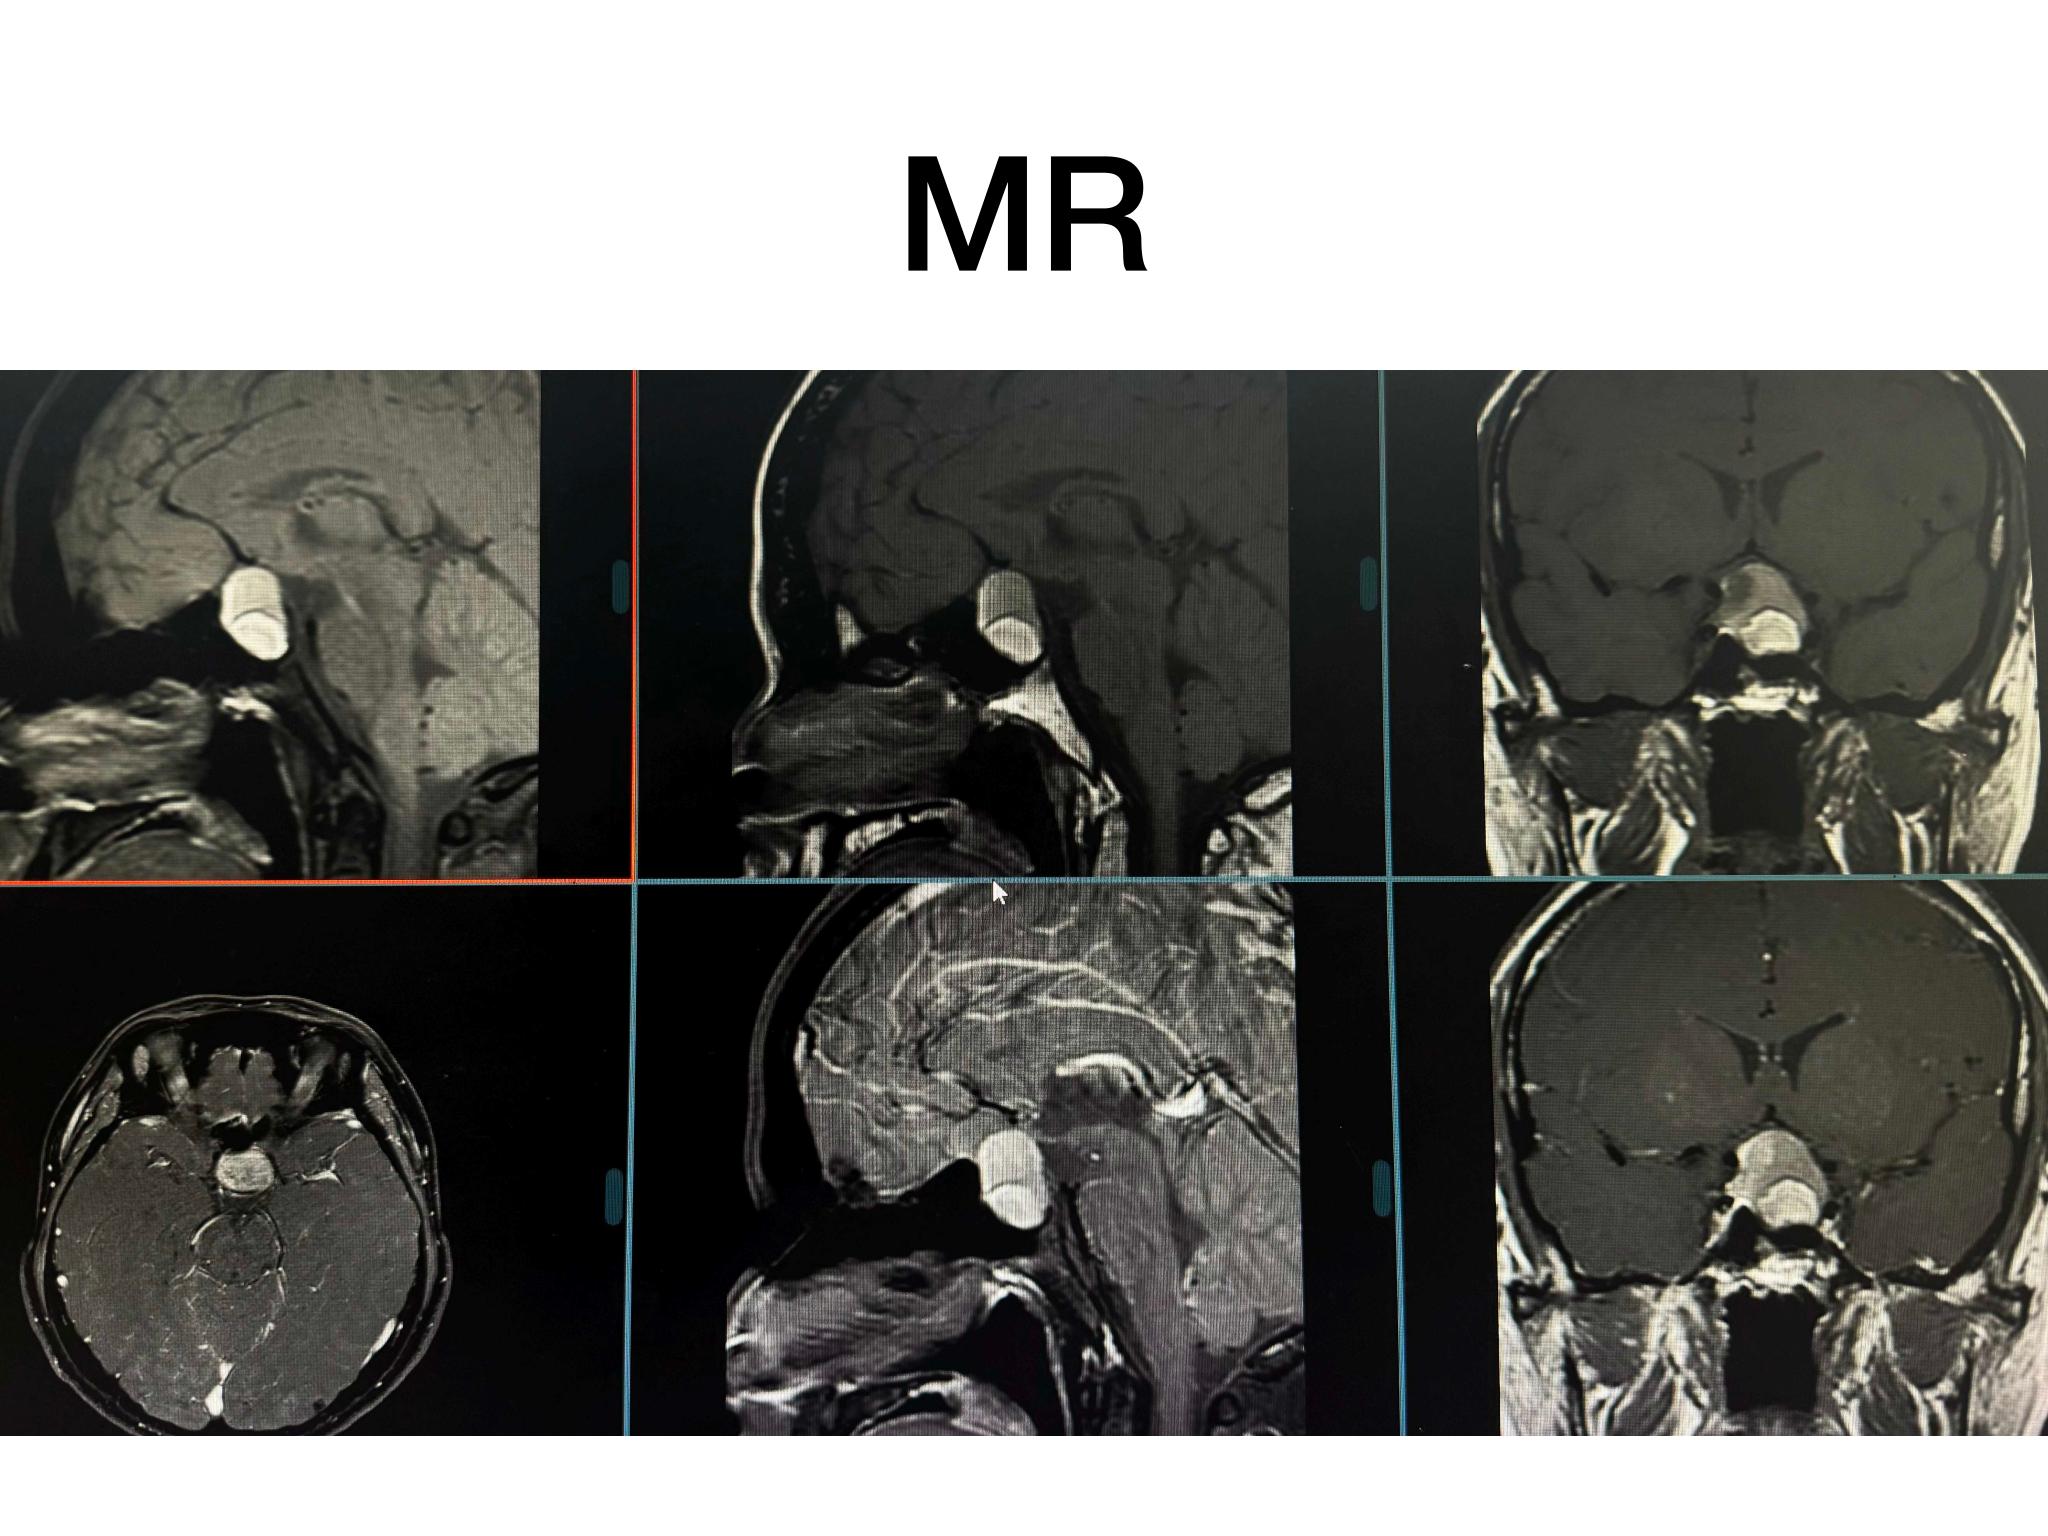

分享一例经鼻内镜泌乳素大腺瘤切除手术,患者青年男性,术前泌乳素>200ng/dl,MR提示大腺瘤合并瘤内出血,手术全切肿瘤,术后泌乳素降至正常,生化缓解,预后良好。